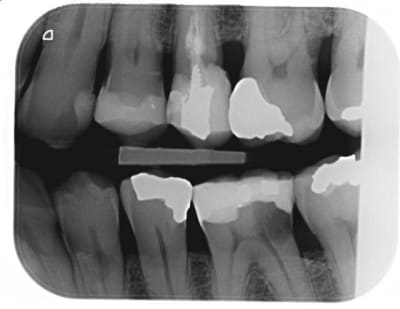

Je compare les btw precedents et tombe sur un hic au niveau de 36 en evolution depuis 2010.

Pour ce que je vois sur les radios, ces soins sont propres, mais pas exceptionnels. Notamment les faces proximales, reconstituées avec des matrices insuffisamment galbées qui produisent un point de contact presque occlusal et qui ne protège pas très bien l'espace inter dentaire en évitant aux aliments de se coincer.

Ceci étant, nous avons tous des patients qui ne passent pas assez les brossettes inter dentaires et déclenchent des caries cervicales incontrôlées.

je m'inquiéterais aussi pour la 25.

face distal de 23 également, y a une petite radio clarté.